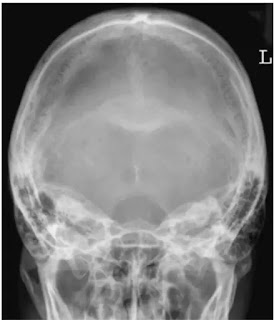

Towne's / Half axial view of skull

इस view को half axial या AP 30° caudal view के नाम से जाना जाता हैं। यह प्रोजेक्शन occipital bone , foreman Magnum और internal audiotory canal की किसी भी प्रकार की pathology को देखने के लिए तथा mastoid की axial position में किया जाता हैं।

Cassette के upper बॉर्डर को इस प्रकार व्यवस्थित करते हैं कि beam angulation के कारण skull का vertex इमेज में शामिल हो। इस प्रोजेक्शन में sphenoid bone की sella turcica foramen Magnum में project होती है। इमेज में occipital bone तथा parietal bone के posterior parts शामिल होने चाहिए तथा lambdoidal suture साफ दिखाई देने चाहिए। skull में कोई rotation नही होना चाहिए।